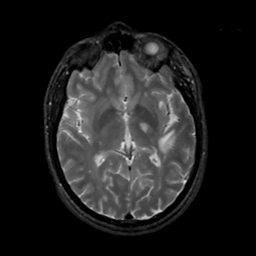

MR Study #2, February 17, 1991 -- Slice #25

[Home][Help][Clinical][Tour 1][Tour 2] Slice 25